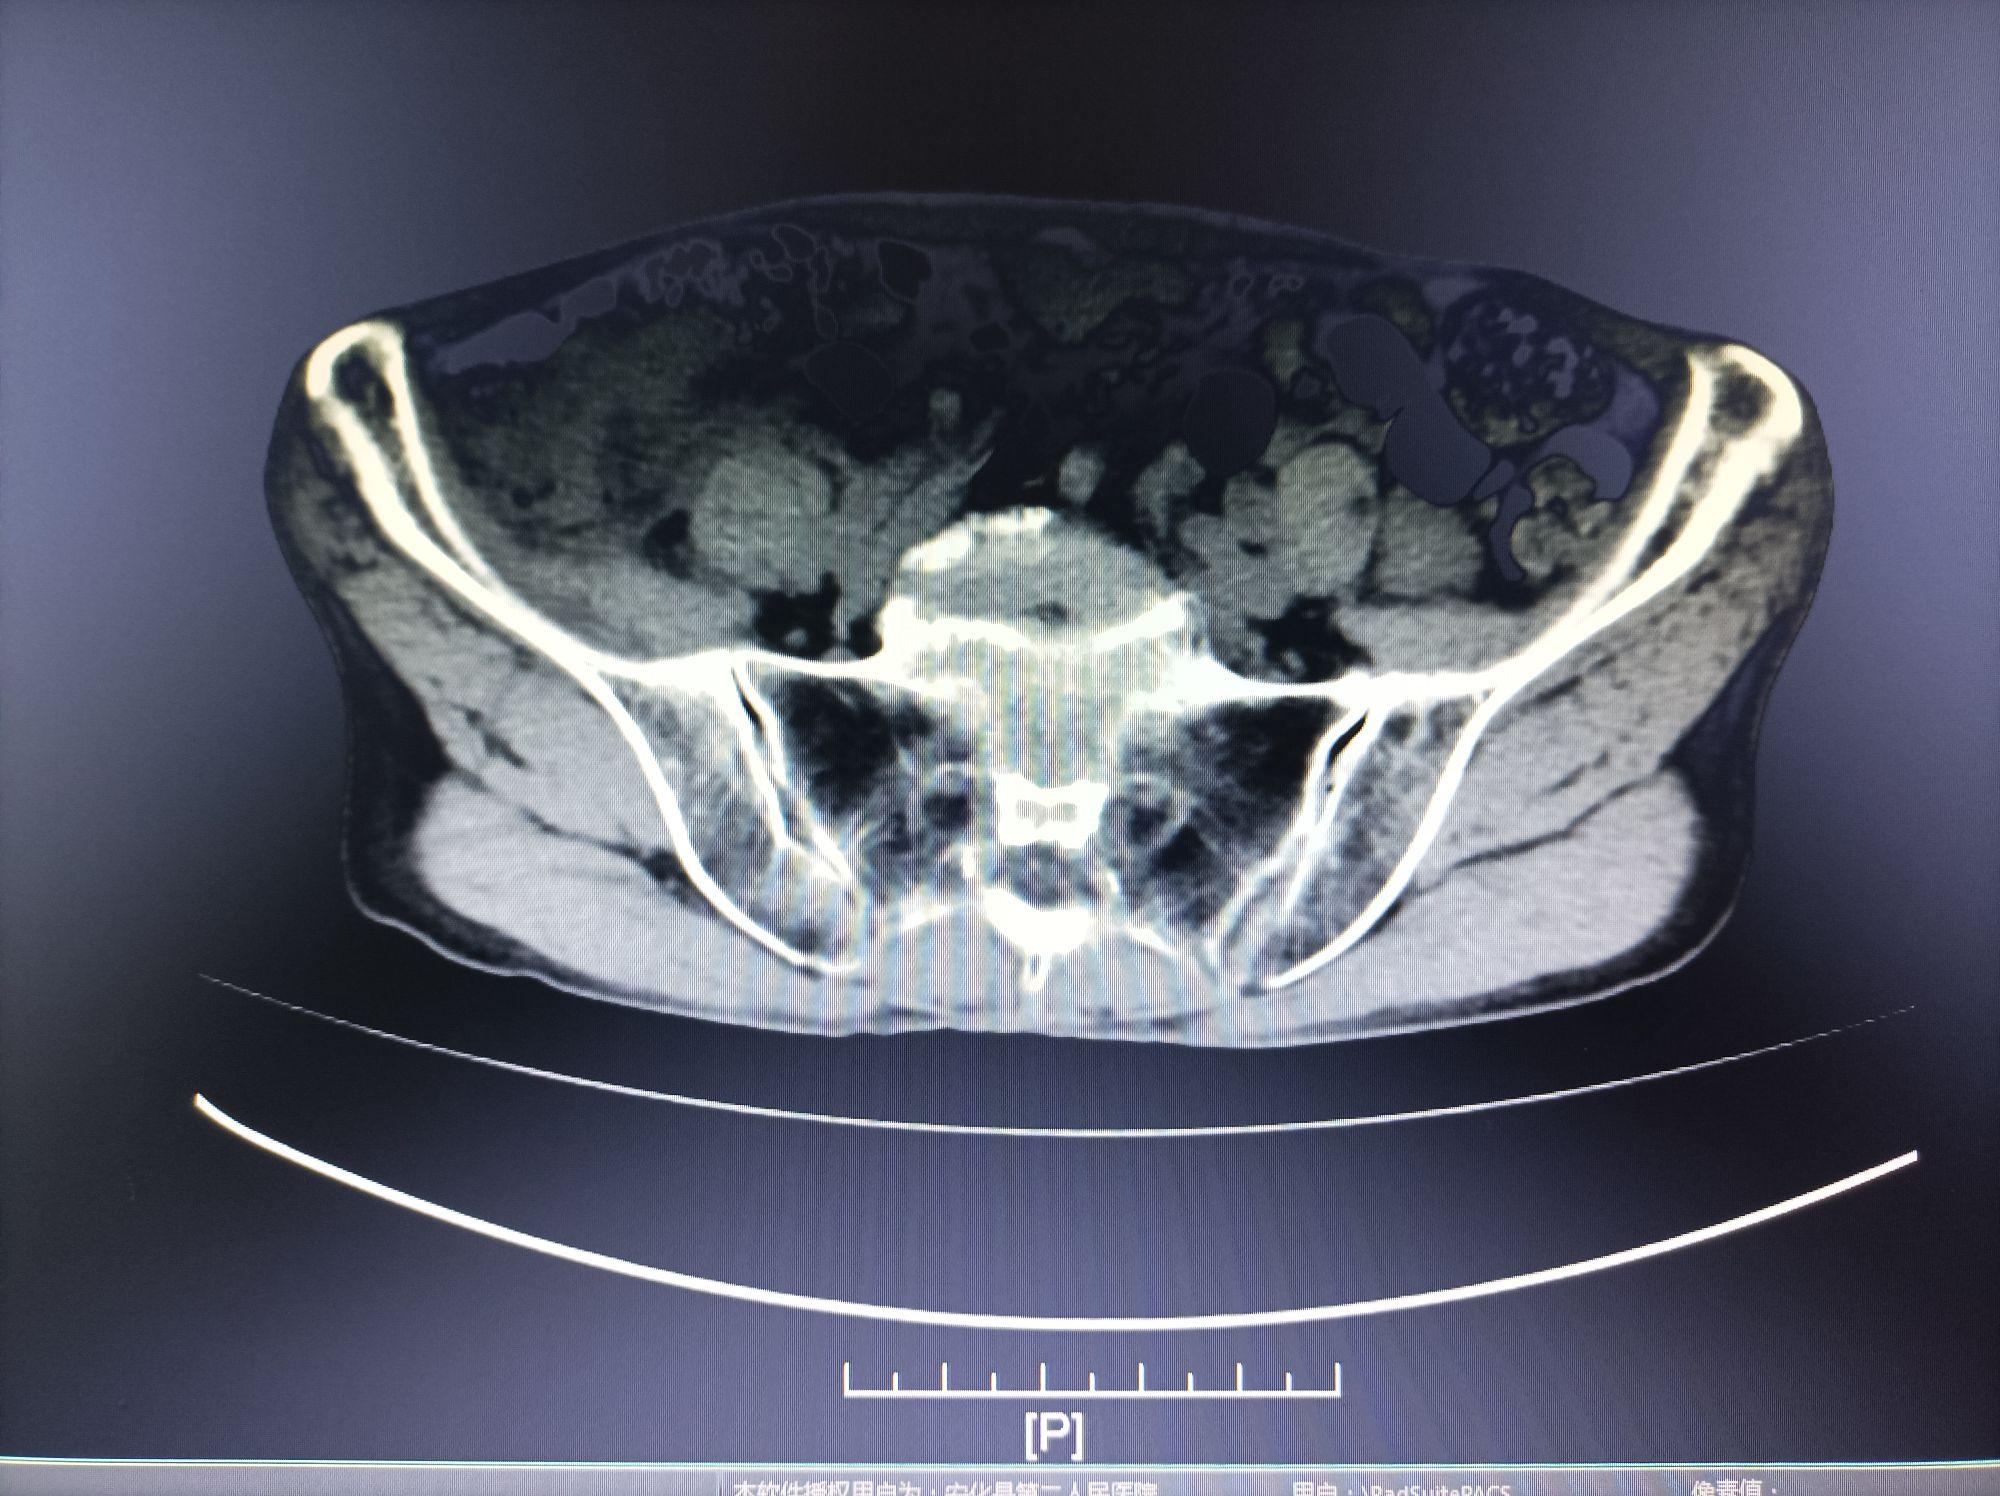

白细胞12.94*10^9/L,中性细胞比率88.900%,血红蛋白89g/L,血小板131*10^9/L,C反应蛋白:5mg/L,超敏C-反应蛋白117.53mg/L;CT检查报告:检查结果:肝多发囊肿。考虑:阑尾脓肿,请结合临床。血型检查检验报告:B;生化检验报告:纤维蛋白原含量4.73g/L,凝血酶原时间12.0Sec,活动度85.05%,国际标准化比值0.960,活化部分凝血活酶时间51.9Sec,凝血酶时间13.4Sec;临检检验报告:白介素654.65pg/ml;生化检验报告:钾4.18mmol/L,钠139.3mmol/L,氯99.90mmol/L,离子钙1.22mmol/L,谷丙转氨酶10.00IU/L,谷草转氨酶19.90IU/L,谷草/谷丙2.00,总蛋白63.9g/L,白蛋白36.30g/L,球蛋白27.60g/L,白球比1.30,总胆汁酸4.7mol/L,总胆红素6.9mol/L,直接胆红素3.20mol/L,间接胆红素3.7mol/L,尿素氮7.31mmol/L,肌酐82.60mol/L,尿酸288mol/L,总胆固醇2.99mmol/L,甘油三酯0.41mmol/L,高密度胆固醇1.74mmol/L,低密度胆固醇1.11mmol/L,肌红蛋白60.0ng/ml,肌酸激酶125.00IU/L,肌酸激酶同工酶10.90IU/L,碱性磷酸酶73.40IU/L,葡萄糖6.38mmol/L,乳酸脱氢酶167IU/L,淀粉酶60.20IU/L普放检查报告:检查结果:腹部立位片目前未见明显异常X线征象,随访。

3.彩超:肝囊肿,前列腺稍大。临检检验报告:白细胞12.94*10^9/L,中性细胞比率88.900%,血红蛋白89g/L↓,血小板131*10^9/L,C反应蛋白5mg/L,超敏C-反应蛋白117.53mg/LCT检查报告:检查结果:肝多发囊肿。考虑:阑尾脓肿,请结合临床。

治疗2周后复查CT:脓腔缩小至2cm*1.5cm,周边肠壁增厚减轻,病情好转出院。1月后门诊复查无异常,拔除引流管。6周后患者出现右下腹隐痛伴腹泻,复查CT示脓腔消失,但回盲部见一窦道与肠管相通(回盲部瘘)。继续瘘管冲洗(生理盐水+甲硝唑),拟3个月后行回盲部瘘修补术(瘘管稳定、炎症消退后)。